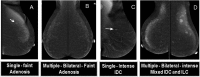

Methods:: The study is a retrospective analysis of the morphology descriptors of 261 enhancing breast lesions identified on CESM in 239 patients. We presented the morphological categorization of the included lesions into focus, mass and non-mass. Further classifications included (1) the multiplicity for "focus" category, (2) the shape, margin and internal enhancement for "mass" category and (3) the distribution and internal enhancement for "non-mass" category. Each morphology descriptor was evaluated individually (irrespective of all other descriptors) by calculating its sensitivity, specificity, positive-predictive value (PPV) and negative-predictive value (NPV) and likelihood ratios (LRs).

Results:: The study included 68/261 (26.1%) benign lesions and 193/261 (73.9%) malignant lesions. Intensely enhancing foci, whether single (7/12, 58.3%) or multiple (2/12, 16.7%), were malignant. Descriptors of "irregular"-shape (PPV: 92.4%) and "non-circumscribed" margin (odds ratio: 55.2, LR positive: 4.77; p-value: <0.001) were more compatible with malignancy. Internal mass enhancement patterns showed a very low specificity (58.0%) and NPV (40.0%). Non-mass enhancement (NME) was detected in 81/261 lesions. Asymmetrical NME in 81% (n = 52/81) lesions was malignant lesions and internal enhancement patterns indicative of malignancy were the heterogeneous and clumped ones.

Conclusion:: We can apply the MRI morphology descriptors to characterize lesions on CESM, but with few expectations. In many situations, irregular-shaped, non-circumscribed masses and NME with focal, ductal or segmental distribution and heterogeneous or clumped enhancement are the most suggestive descriptors of malignant pathologies.

Advances in knowledge:: (1) The MRI BI-RADS lexicon morphology descriptors can be applied in the characterization of enhancing lesions on CESM with a few exceptions. (2) Multiple bilateral intensely enhancing foci should not be included under the normal background parenchymal enhancement unless they are proved to be benign by biopsy. (3) Mass lesion features that indicated malignancy were irregular-shaped, spiculated and irregular margins and heterogeneous internal enhancement patterns. The rim enhancement pattern should not be considered as a descriptor of malignant lesions unless CESM is coupled with an ultrasound examination.